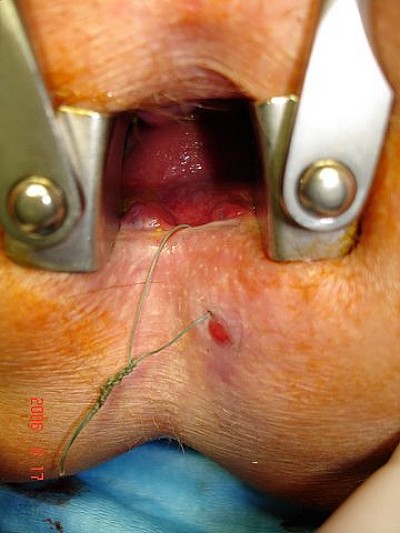

Bilddokumentation - Analfistel-Operationen

Analfistel-Operationen

(trans-, extra-, supra-sphinktäre Verläufe)

Bildergalerie